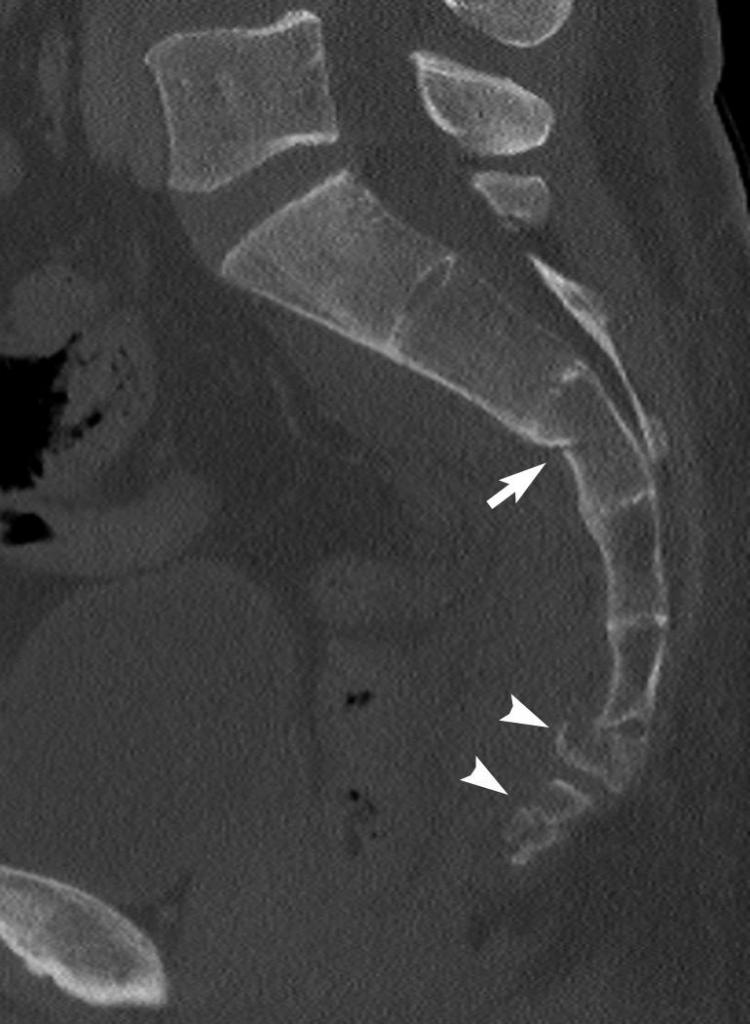

Рентгеновские снимки крестцово-копчикового отдела позвоночника